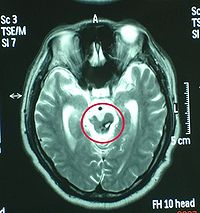

MRI(磁共振成像

一般少用于急性颅脑损伤的诊断。MRI成像时间较长,某些金属急救设备不能进入机房,躁动病人难以合作,故多以CT为首选检查项目。但在某些特殊情况下,MRI优于CT,如对脑干、胼胝体颅神经的显示;对微小脑挫伤灶、轴索损伤及早期脑梗死的显示;以及对血肿处于CT等密度阶段的显示和鉴别诊断方面,MRI有其独具的优势,是CT所不及的。